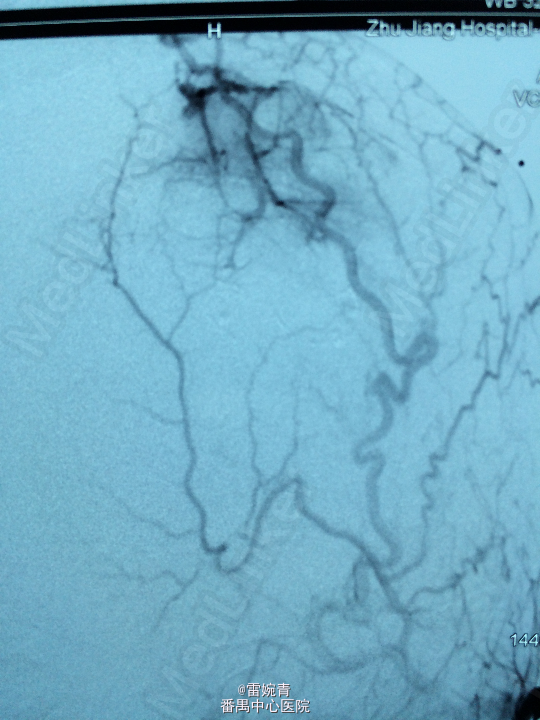

诊断:脑膜瘤 处理:先行DSA检查以明确脑膜瘤的供血动脉情况,见:肿瘤染色,肿瘤主要由左侧眼动脉供血,用Glubran胶将其闭塞,后择期行手术切除治疗。术后病理证实为脑膜瘤。